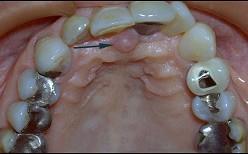

切牙乳突是排列上中切牙的解剖标志、是因为 ( )

切牙乳突是排列上中切牙的解剖标志、是因为 ( )![]()

A切牙乳突的位置变化较小

B切牙乳突位于上颌腭中缝的前端

C切牙乳突与上颌中切牙之间有较稳定的关系

D两个上中切牙的交界线应以切牙乳实为准

E切牙乳突下方为切牙孔